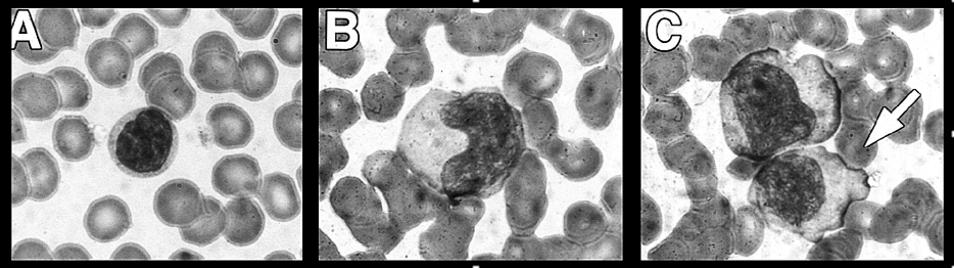

- Laboratory hallmarks of primary infection, clinically symptomatic: - Elevated WBC (10-18K) with lymphocytosis (40->60%) common. - Atypical lymphocytes [Fig] usually comprise 10-30+% of circulating lymphocytes.

Atypical Lymphocytes

A. Normal Lymphocyte

B. Enlarged, atypical lymphocyte with more cytoplasma and bilobed nucleous

C. So-called "Dutch Skirting" caused by red blood cells indenting lymphocyte outer membrane

Source: Paul G. Auwaerter, MD